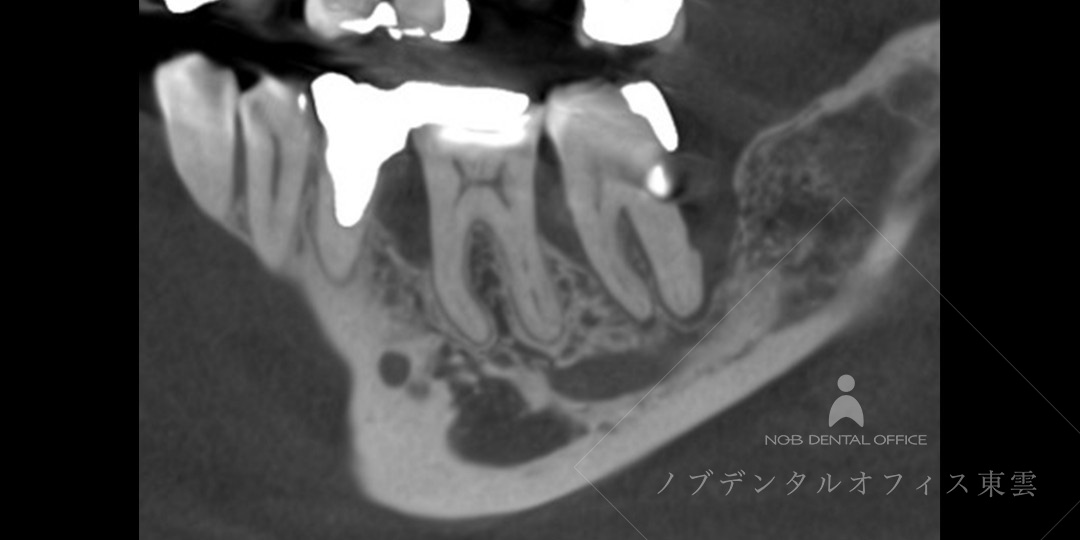

レントゲンおよびCTにて、歯を支える骨の吸収が進行している部分が確認されました。

歯周基本治療後、骨吸収量が大きかったため、自費診療にて歯周組織再生療法(リグロス+骨補填材)を併用しました。

CTで3次元的に確認

骨の吸収部分が大きかったため、CTにて3次元的に確認しました。